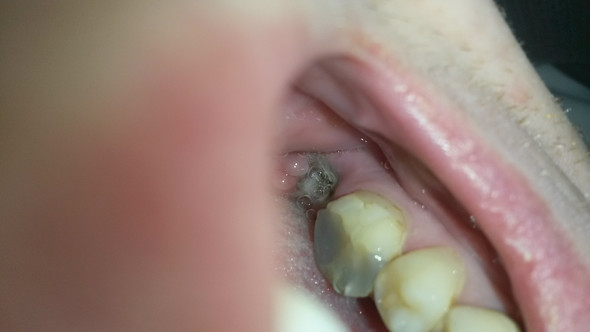

Weißes Zahnfleisch nach Zahnentfernung. Links wirkte die Betäubung prima aber rechts wo auch der zusätzliche Zahn gezogen werden sollte und der Nerv betäubt war wirkte es meiner Meinung nach gar nicht. Nach der Extraktion hatte ich etwas Schmerzen die aber schnell wieder weggingen.

Nur was ist das Schwarze. Er fing mit dem Weisheitszahn oben rechts an. Auch die Zahnwurzeln sind länger.

Nach der Operation wird das Zahnfach gesäubert und ein Wattetupfer eingelegt um die Blutung der Wunde zu stoppen. Und genau an dieser Stelle fühlt es sich auch sehr komisch an. Wie Sie die Wundheilung beschleunigen können.

Die Wunde wird vernäht und nach ca. Ängstlichen Patienten kann der Zahnarzt ein Beruhigungsmittel verordnen. Anschließend ist es möglich den Weisheitszahn zu entfernen. Haben Sie keine Angst davor die Wunde ggfs. Wie Sie die Wundheilung beschleunigen können. Nun hat sich eine Verfärbung in der Wunde gebildetISt das normal. Wenn ein Zahn gezogen wird entsteht im Zahnfleisch eine Wunde. DAS MACHT MIR GROßE SORGEN. Als wäre es entzündet.

Ich habe alles gespürt. Der machte auch sonst abgesehen von ziemlichen Schmerzen und meiner panischen Angst keine Probleme. Dadurch wird die Blutung gestoppt. Noch einmal säubern und ausschaben zu lassen das setzt eine kleine Blutung in Gang die dann zur besseren Wundheilung führt. Nun die Wunde an sich sieht zwar besser aus aber auf einer bestimmten Stellen bildet sich son weißes Zeug. Je nach Größe der Wunde kann sich diese. Nur was ist das Schwarze.